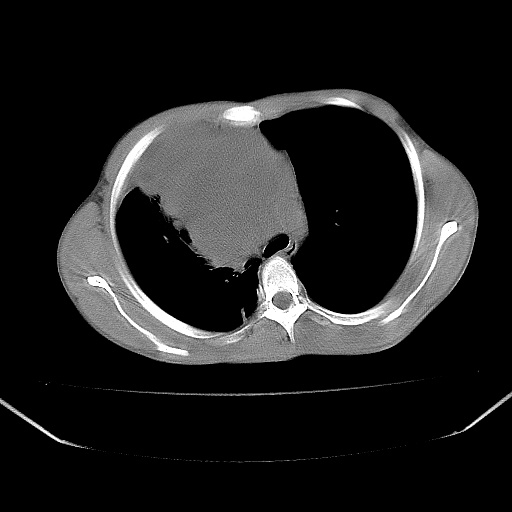

以下是引用zjzjr在2008-7-20 12:57:00的发言:[br]考虑为生殖源性肿瘤(内胚窦瘤),侵袭性胸腺瘤可能性大;右侧少量胸腔积液。

以下是引用xinliheng001在2008-7-20 21:17:00的发言:[br]右纵隔巨大分叶状软组织均质密度肿块,右上肺叶受压明显,纵隔右移、胸膜受累有少量积液和结节样增厚。应增强扫描一定会有更具诊断价值的信息。

以下是引用xinliheng001在2008-7-20 21:17:00的发言:[br]右纵隔巨大分叶状软组织均质密度肿块,右上肺叶受压明显,纵隔右移、胸膜受累有少量积液和结节样增厚。应增强扫描一定会有更具诊断价值的信息。